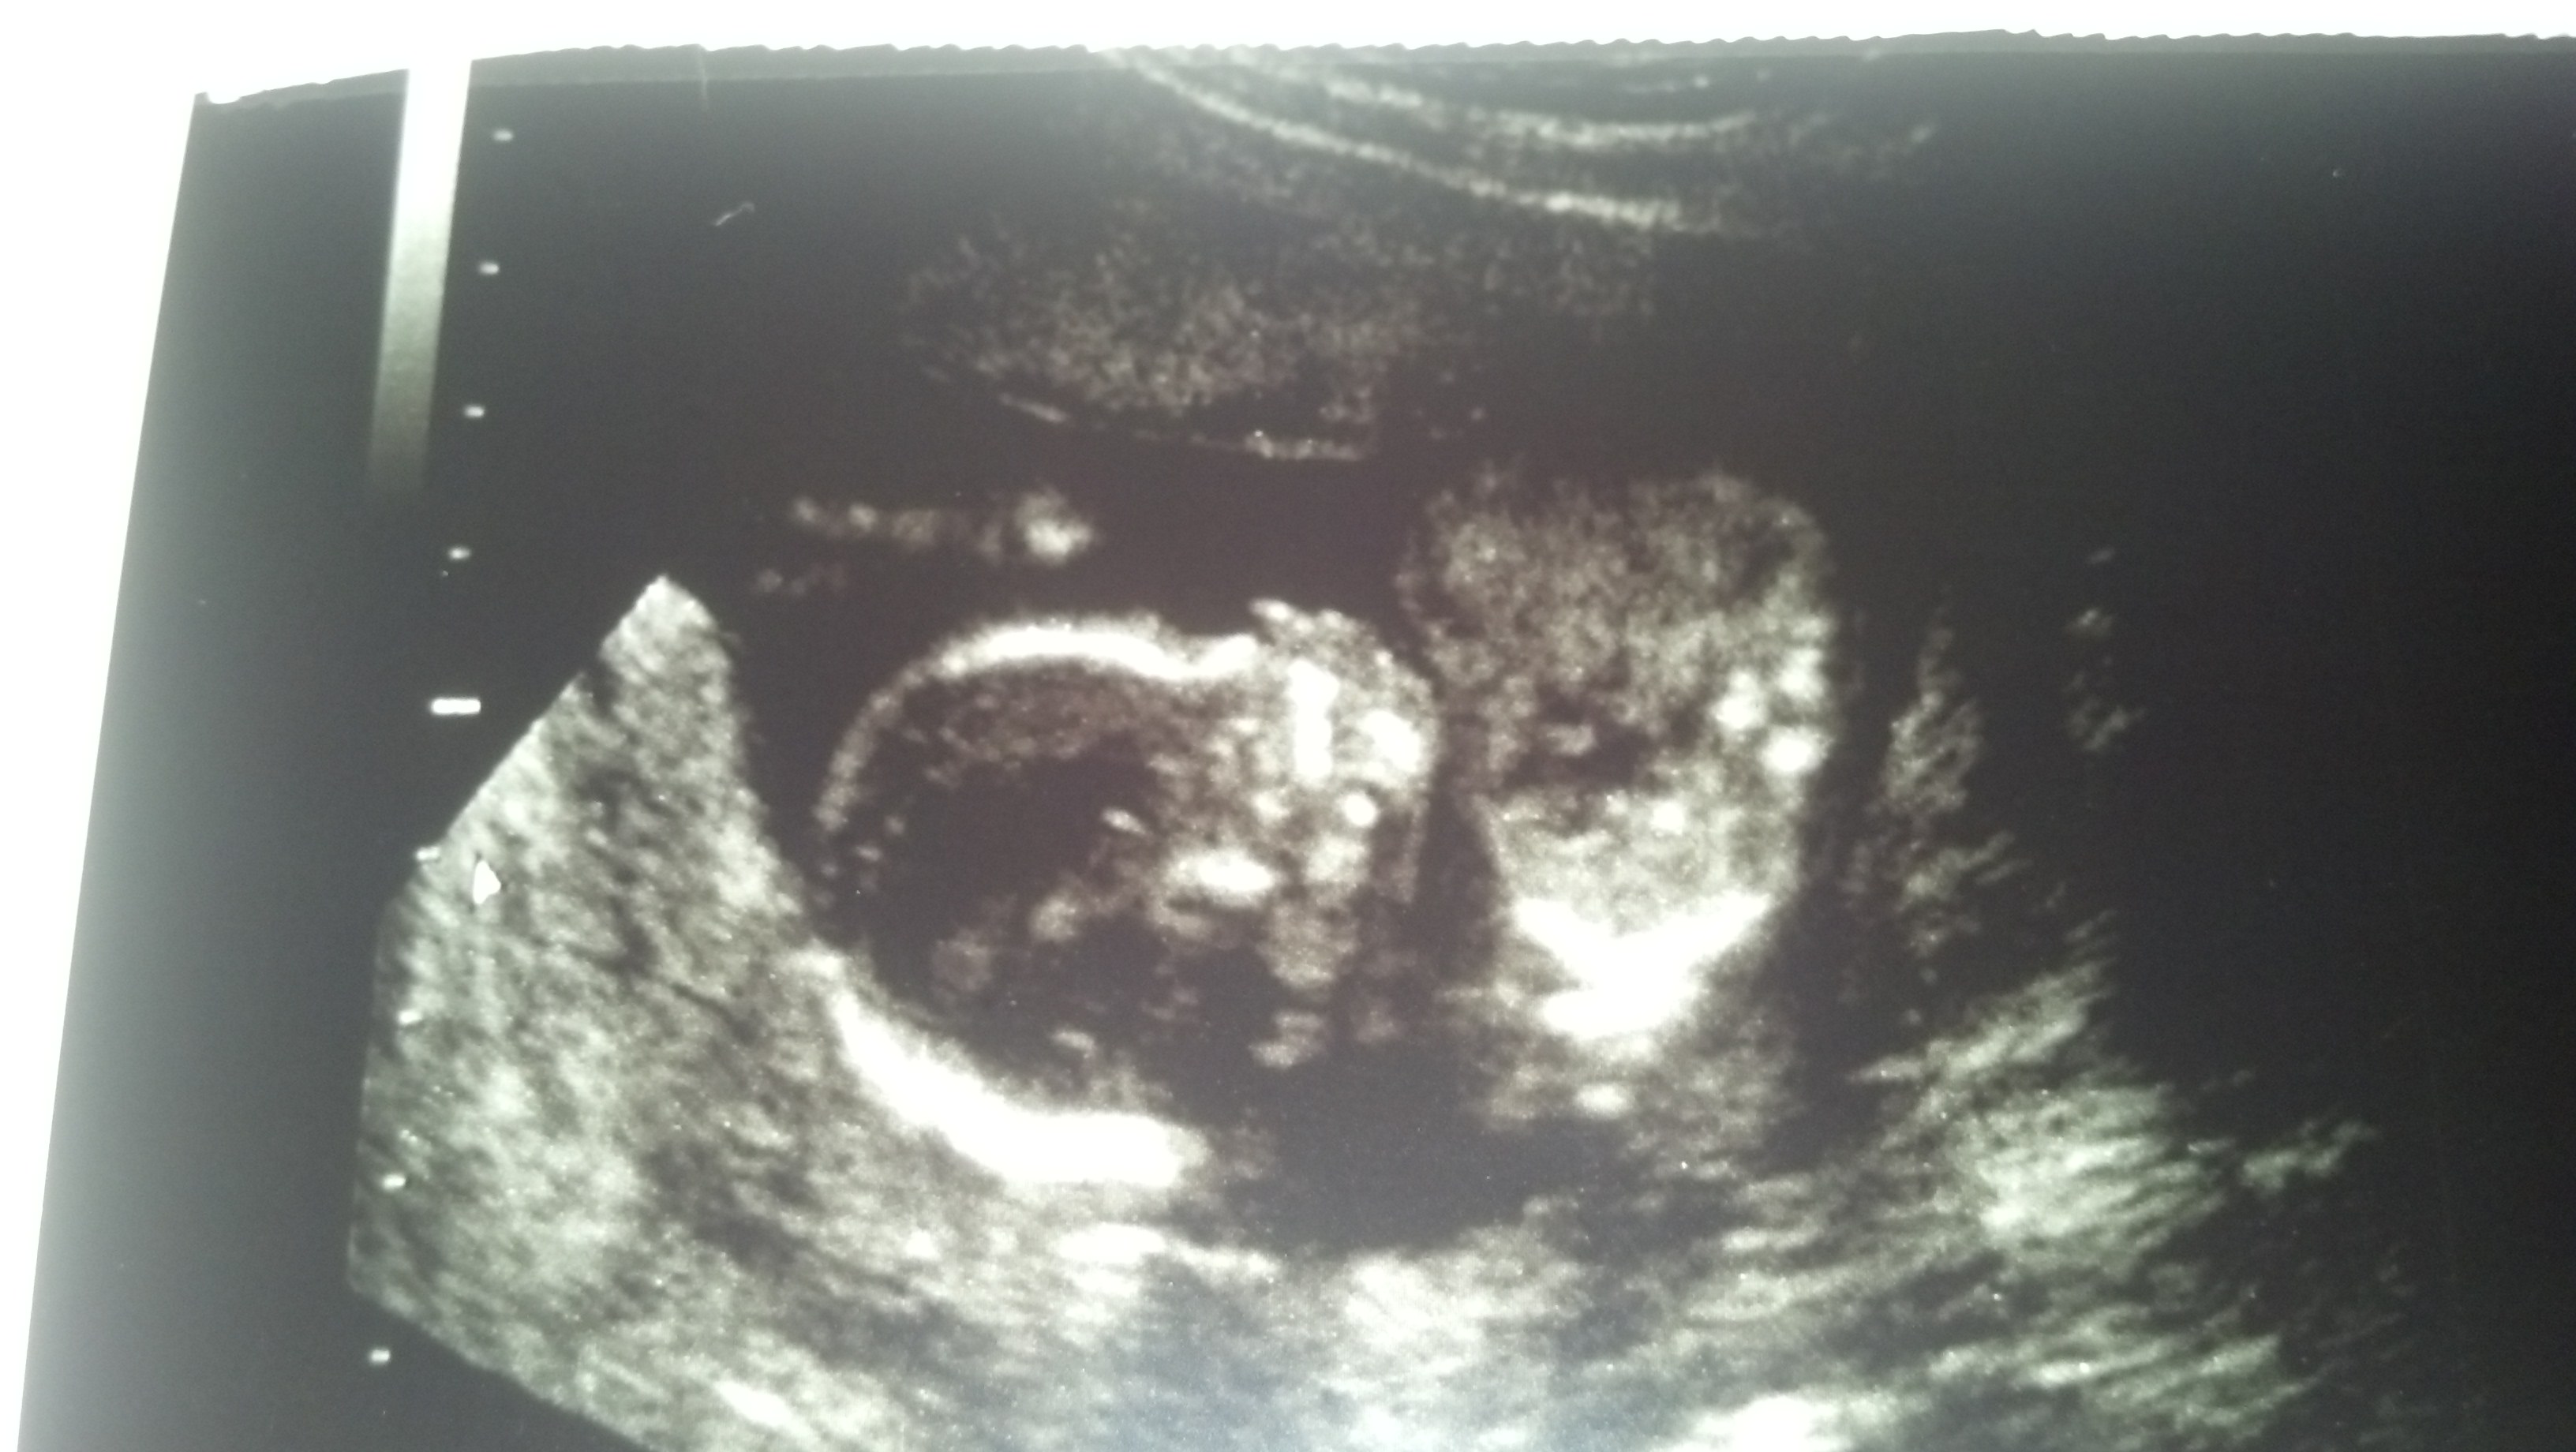

Well, I might have driven 2 hours away for a 10 min session but she checked all angles and saw three lines. SO I guess I am getting my first princess. I feel like maybe it hasnt sunk in yet cz I just feel like its a practical joke, that I couldn't be having a girl after all this time and coming up with my 2 boys. Ig I just don't really believe it yet.Attachment 13189Attachment 13190